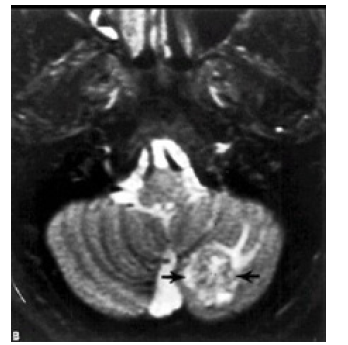

Enhancement of the tumor was seen in all the 16 patients in whom an I. V. contrast was used. 6 patients (37.5 %) showed ring like enhancement and 10 patients (62.5 %) showed heterogeneous enhancement.Perifocal edema was noticed in all the cases. It was marked in 6 patients (24 %), moderate in 15 patients (60%), and mild in 4 patients (16%). The metastases were supratentorial in 14 patients (56 %), infratentorial in 5 patients (20%), and both supraand [26,27,28] infratentorial in 6 patients (24%). Hydrocephalus was seen in 5 patients (20%), all of them have an infratentorial brain metastasis. It was due to compression of the 4thventricle by the metastasis leading to dilatation of the lateral and 3rd ventricles (triventricular hydrocephalus) (Figure 6 ).

MRI: This was done for only 11 cases according the availability of this study in these hospitals. T1 and T2 studies done for all of those taken the MRI study but Gadolinium contrast study done for only 5 of those cases. (Figure 7& Figure 8 ) Brain MRI T1 and T2 studies